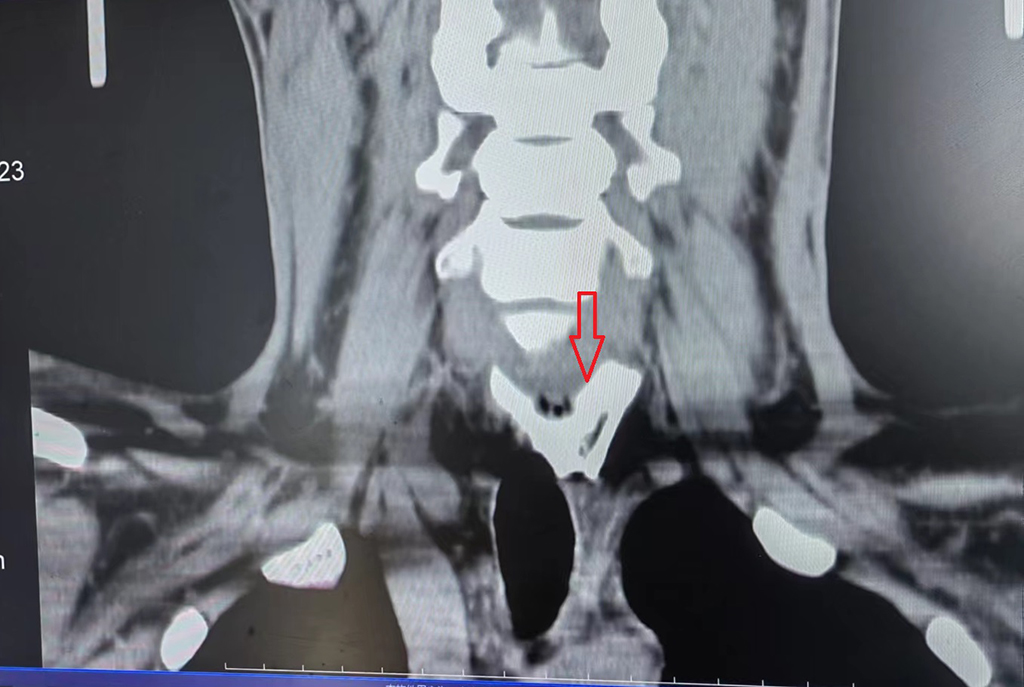

食管冠状位CT影像

当天,陈先生的母亲为其煮了一碗螺蛳粉,因不知晓这碗螺蛳粉是用骨头汤煮的,粗心的陈先生误吞下一块“巨型”猪骨头。这块猪骨呈长方形,长约4.1cm,宽约3.8 cm,厚度约3mm,四角尖锐,正好卡在食管入口的下方。入院时,患者十分痛苦,说话困难,连口水都无法吞咽,并且“巨型”骨尖锐锋利的边角随时都有穿通食管的可能,一旦造成食管穿孔并发感染,陈先生将会面临生命危险。